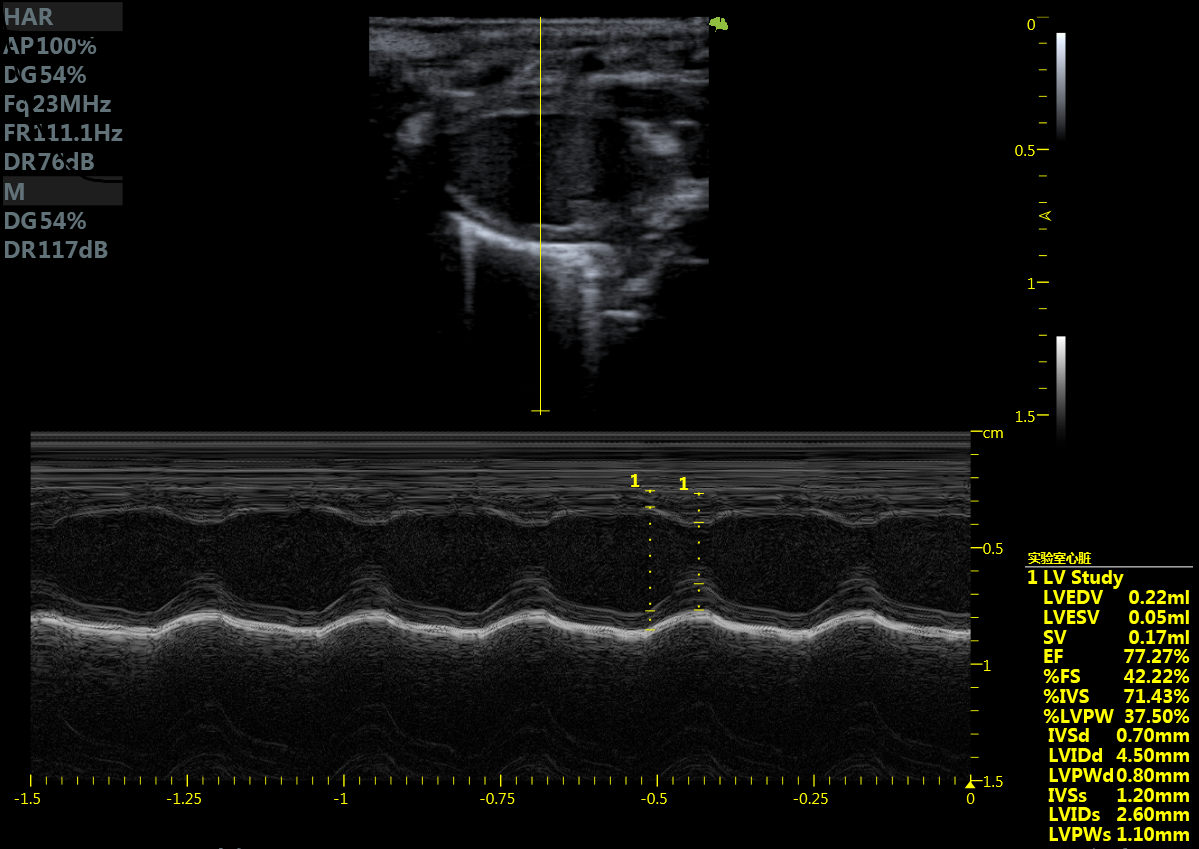

小鼠长轴M型 小鼠短轴M型

大鼠短轴M型 大鼠长轴M型